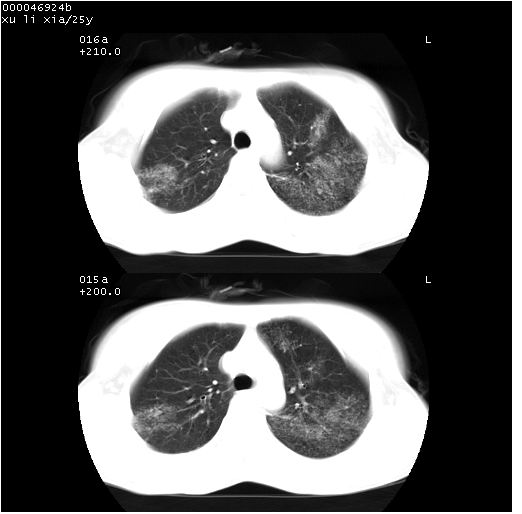

患者 女,25岁。因“左侧卵巢肿瘤”术前胸片偶然发现两肺病变。平素无明显不适,无呼吸系统症状及体征,无传染病史。

cr x线胸片提示:两肺感染性病变(结核可能性大)。

胸部ct轴位平扫(层厚10mm,螺距1.5,重建间隔10mm),图像如下:

(注:上级医院会诊胸部ct片——考虑为肺部真菌感染。)

病灶呈地图样分布于肺外围,与正常组织分界清晰+弥漫性磨玻璃影中见小叶间隔增厚呈碎石路样表现+年轻女性,无明显临床症状=肺泡蛋白沉积症?